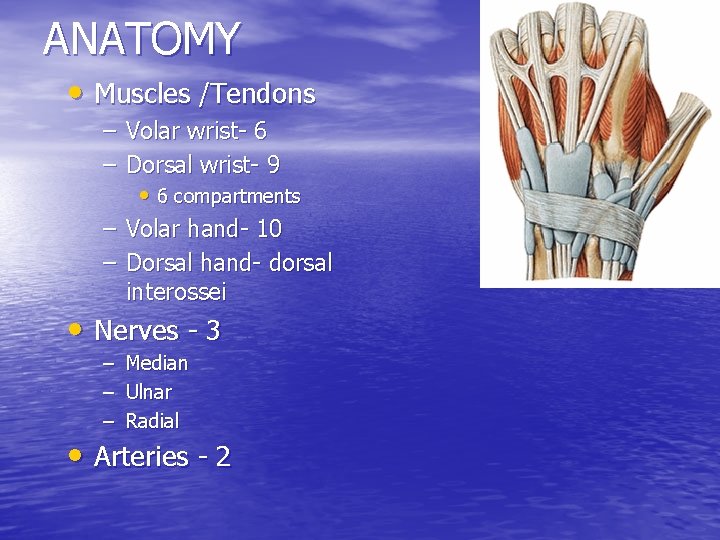

ANATOMY • Muscles /Tendons – Volar wrist- 6 – Dorsal wrist- 9 • 6 compartments – Volar hand- 10 – Dorsal hand- dorsal interossei • Nerves - 3 – – – Median Ulnar Radial • Arteries - 2